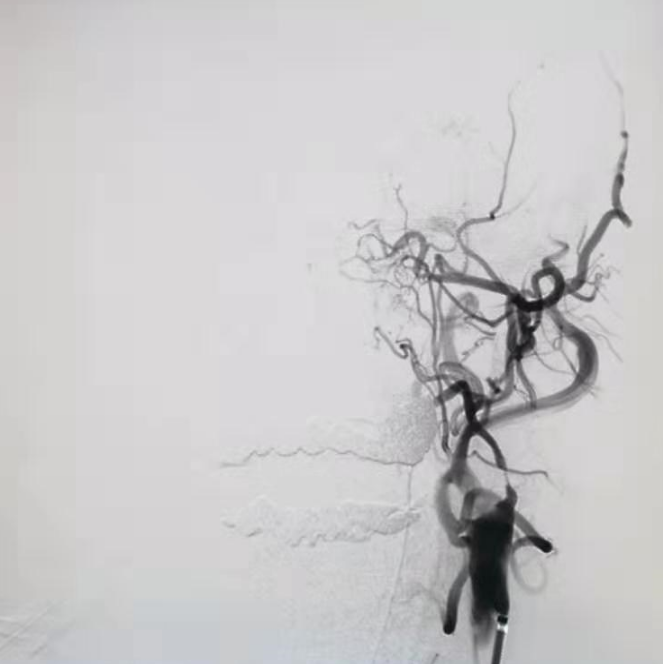

DSA显示ICAO

微导管造影证实MCAO

手术过程

中间导管配合在长鞘和小球囊的配合下穿过迂曲夹层的颈内动脉。

微导管微导丝越过MCA闭塞段,置入取栓支架支架。

微导管微导丝穿过夹层段,4.0×20mm球囊再次反复贴附夹层段,促进内膜贴壁。

造影观察,管腔狭窄较前好转,血流状态稳定,结束手术。